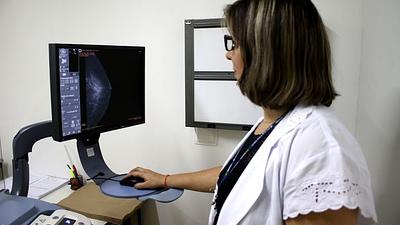

Modelo de inteligência artificial analisa mamografias para avaliar risco do desenvolvimento da doença. Técnica pode ajudar a identificar casos não detectados pelo exame tradicional.

A ferramenta de IA foi aplicada em tempo real e envolvendo um grupo ampliado de pessoas, em vez de ser utilizada posteriormente como vinha sendo feito até agora.

Os laudos dos exames de mamografia realizados no Centro Carioca de Diagnóstico e Tratamento por Imagem (CCDTI) são avaliados e assinados por profissionais médicos capacitados, no entanto, a IA auxilia na identificação de possíveis lesões difíceis de serem vistas.